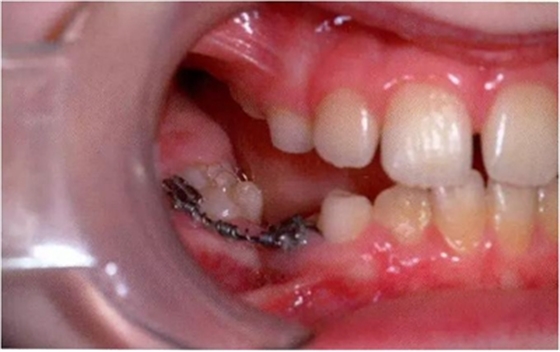

當(dāng)下沉乳牙需要拔除時(shí),應(yīng)當(dāng)注意這樣的牙齒由于跟牙槽骨有粘連,所以會(huì)有骨折的傾向。應(yīng)當(dāng)考慮使用無創(chuàng)拔牙技術(shù),即在使用牙鉗拔除之前先設(shè)法松解破壞牙槽骨與粘連牙之間的骨性結(jié)合。嚴(yán)重下沉或者難以入路的牙齒有必要使用外科手術(shù)拔牙。如果鄰牙傾斜可能引起嚴(yán)重的牙弓長(zhǎng)度喪失,對(duì)合牙伸長(zhǎng)和阻礙繼承恒牙萌出的話,也應(yīng)當(dāng)拔除下沉乳牙。當(dāng)使用正畸裝置時(shí),可以開展間隙,改進(jìn)入路。因此下沉乳牙的管理也可以被納入到一個(gè)全面的治療計(jì)劃中(圖10 )。這樣就可以允許有更直接的下沉牙拔除入路,甚至可以促進(jìn)下沉牙的萌出并避免進(jìn)一步的干預(yù)。

圖10:臨床照片展示使用固定可調(diào)正畸裝置糾正傾斜的下頜磨牙